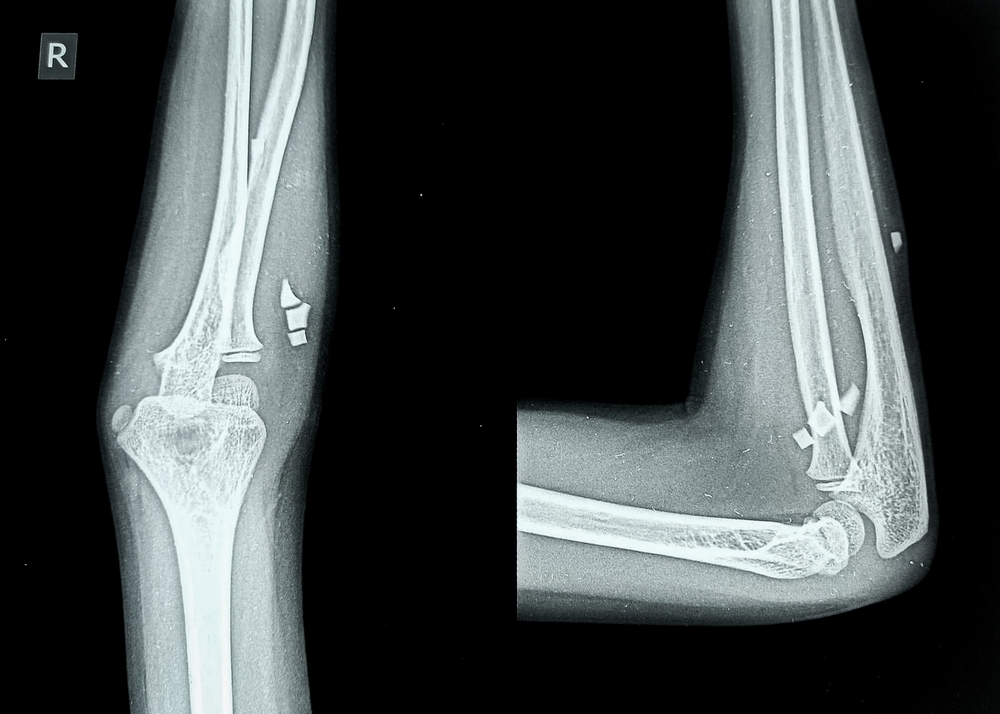

Рентгенографию локтевого сустава проводят в прямой и боковой проекциях. При получении снимка в прямой проекции больной находится боком к диагностическому столу, кладет руку ладонью вверх и разгибает ее в локтевом суставе. Чтобы получить изображения в боковой проекции, пациент остается в том же положении, руку размещает вниз ладонью и сгибает в локте под прямым углом. Для получения фотографий в аксиальной проекции изображения делают во время максимального сгибания руки в суставе, локоть при этом фиксируется подставкой.

Анализируя полученные рентгеновские снимки, врач оценивает состояние всех структур локтевого сустава, костей, рядом расположенных тканей (связки, синовиальная оболочка, капсула, сухожилия). Доктор изучает диаметр суставной щели, конгруэнтность суставных поверхностей. Сравнивая значения с нормой, специалист диагностирует разные патологии, определяет их характеристики: форма, локализация, распространенность, размеры, отличительные черты. Собрав все сведения, доктор пишет заключение.

С помощью рентгена локтевого сустава в двух проекциях можно обнаружить переломы костей, инородные тела, вывихи и подвывихи суставных поверхностей, трещины костных структур, артроз, остеомиелит, артрит, аномалии развития. Рентгенологическое обследование актуально в плане выявления воспалительных и инфекционных поражений, костных разрастаний, кальцинатов, уплотнений и новообразований, разрыва связок, остеопороза.